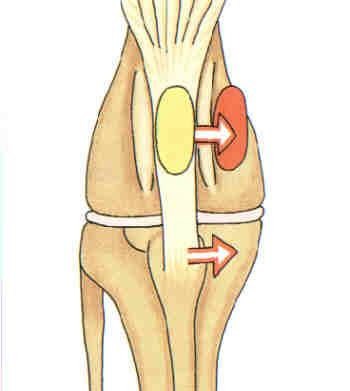

Das intakte vordere Kreuzband hält im Kniegelenk beim Abrollen den Oberschenkelknochen auf dem Schienbein fest.

Nach einem Riss des vorderen Kreuzbands wird der Oberschenkelknochen nicht mehr auf dem Schienbein festgehalten. Der Abrollvorgang wird verlängert und der Meniskus (rosa) kommt unter schmerzhaftern Druck.